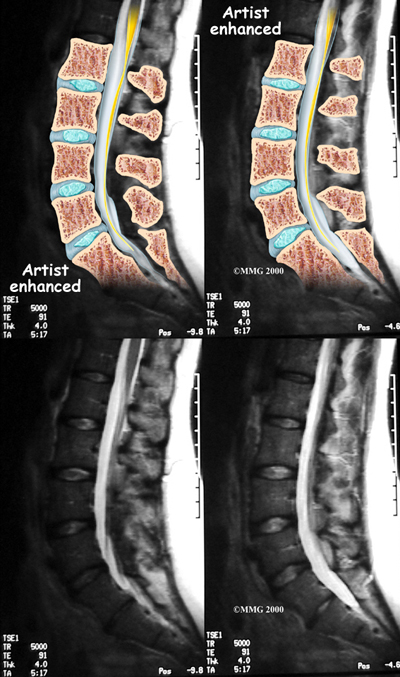

If there are symptoms suggesting the spinal nerves or spinal cord are in danger, an MRI scan may be recommended to look at the spine more closely. The MRI scan uses magnetic waves to create pictures of the lumbar spine in slices. The MRI scan shows the lumbar spine bones as well as the soft tissue structures such as the discs, joints and nerves. MRI scans are painless and don't require needles or dye. Specialized MRI techniques are now available that can detect inflammatory changes in the sacroiliac and vertebral joints long before they appear on x-rays.